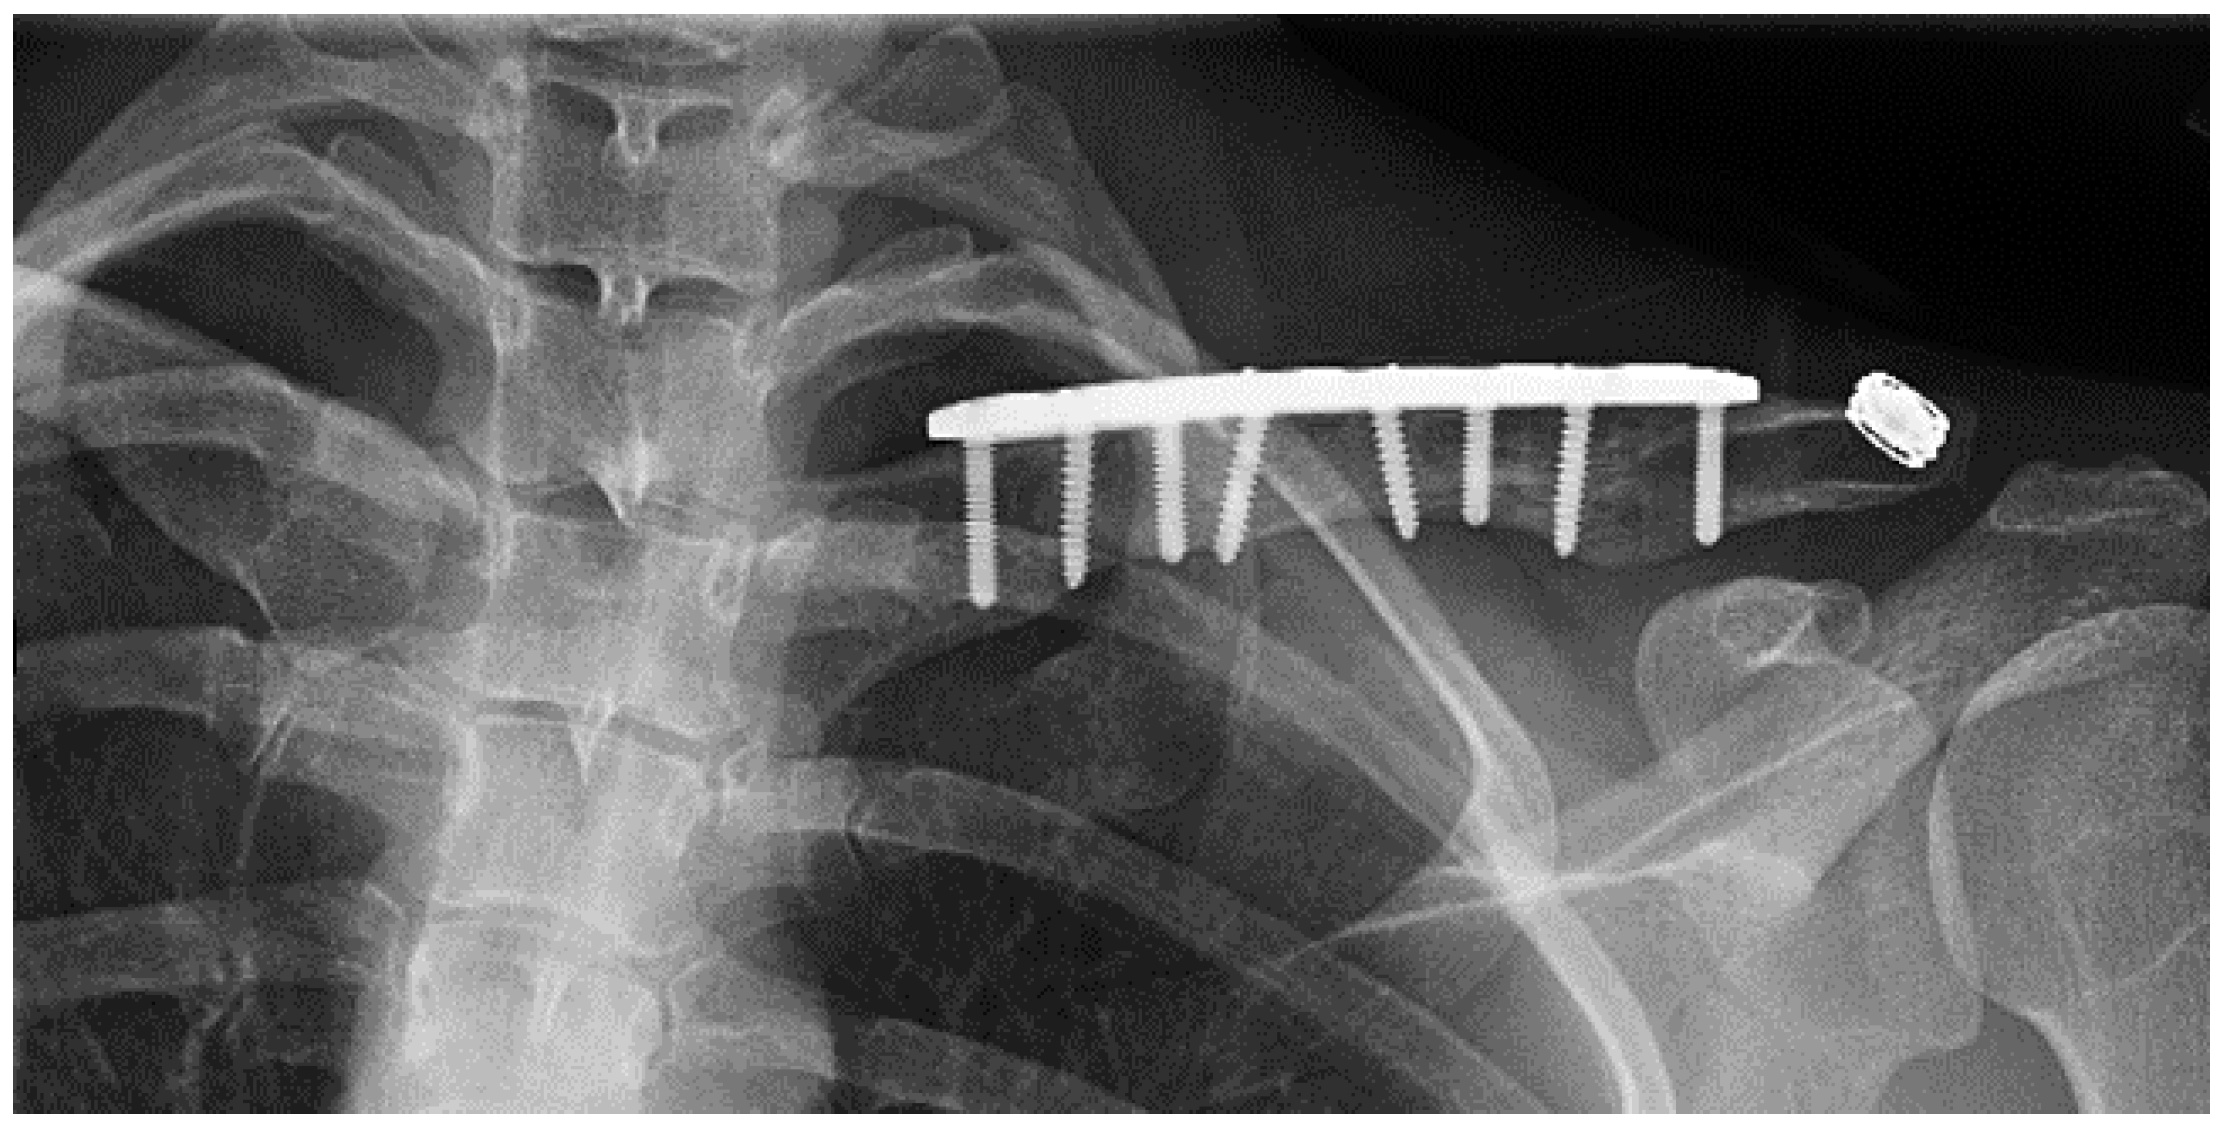

A 27 year-old female who had suffered a left clavicular fracture that was repaired previously presented with left upper extremity numbness and pain for one week. The symptoms occurred spontaneously and were intermittent throughout the week. She experienced no relief with analgesics. She presented to our Emergency Department. Brachial, ulnar and radial pulses were non-palpable. An arterial duplex revealed an occlusive thrombus of the brachial artery at the mid-humerus that appeared to be associated with the patient’s previous clavicular repair (Figure 5). A CT angiogram subsequently revealed a subclavian artery aneurysm adjacent to one of the screws from her prior clavicle repair (Figure 6).

Figure 5.

Arterial thoracic outlet syndrome (ATOS) patient with metal plate and screws after a prior clavicular fracture—the screws are abutting the thoracic outlet.